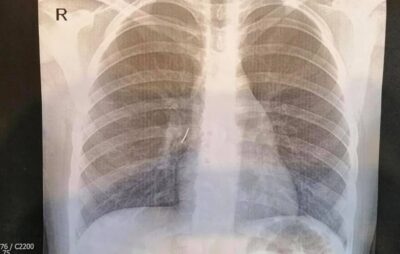

Маленька пацієнтка з канцелярським цвяхом потрапила до нас в ОХМАТДИТ сьогодні вночі. Її до нас привезла швидка з Ходорівської міської лікарні. Дитині зробили рентген-знімок і слова дівчинки про стороннє тіло у бронху підтвердилися – на знімку чітко видно цвях.

“Ми виконали ригідну трахеобронхоскопію під наркозом. Спеціальними ендоскопічними інструментами – щипцями під оптичним контролем – з правого проміжного бронха дитини ми дістали канцелярський цвях з пластмасовою частиною і гострим вістрям. То було непросто, адже пластмасова частина цвяха повністю перекрила бронх так, що нижня доля правої легені майже не функціонувала”, – розповів Олександр Колодій, який займався порятунком дитини.

- Фото: ОХМАДИТ/ФБ